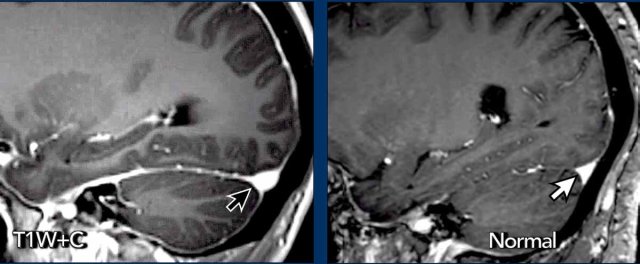

Diffuse smooth dural thickening is sometimes visible on FLAIR images (arrow) but is more easily seen on post-contrast T1W-images.

Convex border transverse sinus

In SIH the lower border of the transverse sinus can be convex (black arrow).

In normal conditions the transverse sinus usually has concave borders (white arrow).

The explanation for the venous engorgement and the concave borders of the transverse sinus is that the low volume of CSF in the cranial vault in patients with SIH is compensated by an increase in volume of the cerebral veins.